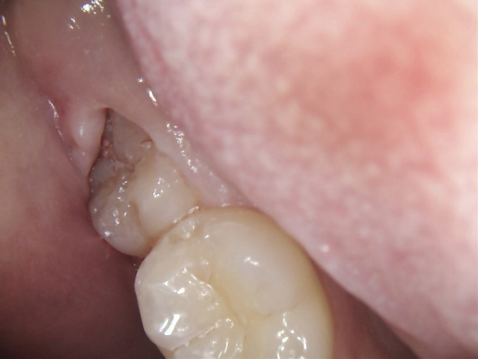

1.上も下も親知らずが半分しか頭を出さず、その周りに磨き残しが出来てしまいます

親知らずに歯肉がかぶさり、ブラッシングが思うように出来ません。虫歯と歯槽膿漏になる可能性が高くなります。

前の歯の陰に隠れて親知らずまで歯ブラシが届かず、汚れがいっぱい残っています。